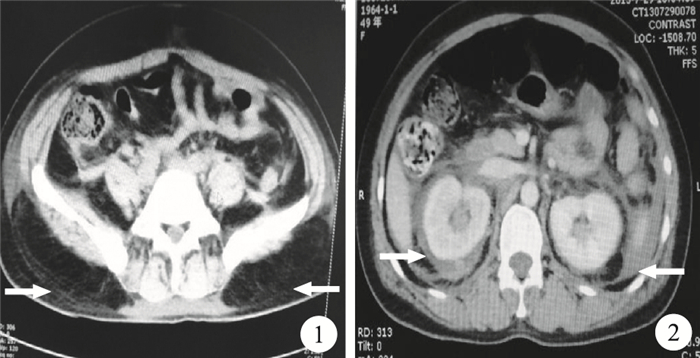

患者,女,49歲,因“雙下肢脹痛1周”于當地醫院入院。B超提示左下肢靜脈血栓,予以長期口服華法林2.5 mg抗凝,1次/d。2周后緩解不明顯,自行加量至5 mg,1次/d,持續約2個月。未復查凝血酶原時間(PT)。后因腹痛、腹脹20+ d,加重3 d,伴血尿、下肢腫痛不適并雙下肢活動受限,在當地醫院治療,未見明顯好轉,由急診科收入我科。入院后留置導尿,可見肉眼血尿。凝血功能檢查:PT>120.0 s,活化部分凝血酶時間168.4 s,空腹血糖4.78 g/L。尿常規:潛血(+++),RBC 250/HP,蛋白質(++++)。入院后查體:心率136次/min。腹部膨隆,右側腹部壓痛、反跳痛及肌緊張,且以右下腹為重,腸鳴音減弱。腰背部叩痛明顯。雙下肢腫脹明顯,皮溫對稱,雙側股動脈、腘動脈及足背動脈搏動對稱,雙下肢輕度凹陷性水腫。腹部CT檢查提示腹腔、腹膜后及盆腔積液,腹膜后感染?雙腎輕度積水,雙側輸尿管上段擴張,雙側胸腔少量積液(圖 1、2)。入院后診斷為自發性后腹膜出血、泌尿系出血、腹腔及胸腔出血。處理:立即靜脈輸入維生素K1及輸入新鮮冰凍血漿,持續治療約3周時間,患者腹痛緩解,血尿停止,雙下肢腫痛緩解。復查腹部CT,提示后腹膜血腫明顯吸收,復查PT恢復正常。

華法林是常用的香豆素類抗凝血藥之一,其化學結構與維生素K相似,作用機制可能通過競爭性拮抗維生素K,影響凝血酶原Ⅱ、Ⅶ、Ⅸ、Ⅹ因子的合成,使凝血時間延長。臨床表現主要是出血傾向。華法林抗凝劑量過量導致后腹膜出血、泌尿系出血、腹腔及胸腔出血是少見的嚴重抗凝并發癥,尤其是以后腹膜出血極少見,易被誤診,病死率較高,可表現為腰、腹部疼痛、低血容量性休克、股神經缺血性病變、腹腔間隔室綜合征等。約1/3的患者表現為劇烈疼痛、休克和非搏動性腹部包塊Lenk三聯征。本例患者首發癥狀為腰部及下肢疼痛,并伴隨下腹疼痛及血尿癥狀,可能與腹膜后血腫壓迫股神經有關;而當患者屈髖關節時可減輕下肢疼痛不適是因減輕血腫對股神經的壓迫。患者在當地醫院就診時,因雙下肢腫脹明顯而診斷為下肢深靜脈血栓,因此繼續使用華法林抗凝并加大劑量,導致病情加重,泌尿系、腹腔及雙側胸腔少量出血。后腹膜出血診斷首選腹部CT檢查,其可以準確定位出血的部位、血腫大小及其在軟組織中的延伸范圍,增強CT可以評估保守治療的效果,明確是否需要介入治療。復習文獻發現,大多數后腹膜出血的患者伴有下肢腫脹、疼痛,易誤診為下肢靜脈血栓、腰椎間盤突出。因此,進行抗凝治療的患者,出現不明原因的下肢腫脹、疼痛時,應考慮到后腹膜出血的可能性,并應立即完善凝血功能、下肢血管彩色多普勒超聲、腹部增強CT等檢查,以明確診斷。若后腹膜出血被誤診為下肢靜脈血栓而加強抗凝治療,可能導致嚴重后果。后腹膜出血的保守治療包括停止和逆轉抗凝治療、液體復蘇以及輸血。